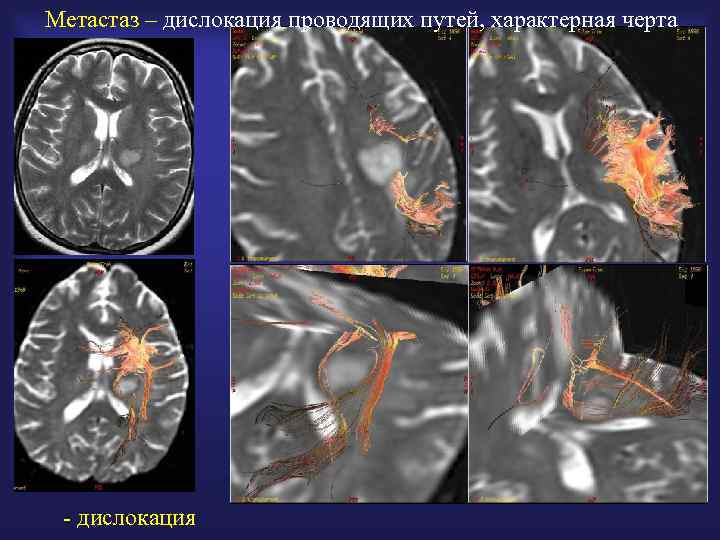

Метастаз – дислокация проводящих путей, характерная черта - дислокация